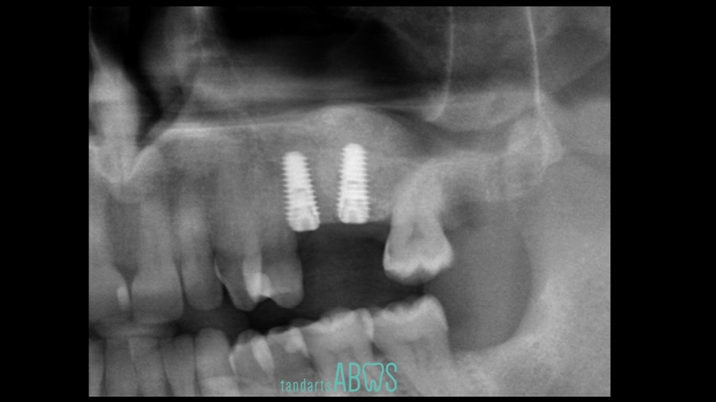

Clinical case: Installation of dental implants in complicated anatomic conditions using crest lifting methods

- Courtesy of Dr.Alexander Lysov, Russia -

Keywords

AnyRidge, complicated anatomic conditions, crest lift, MICA Kit, Dr. Alexander Lysov, bone regeneration, GBR, #26, maxillary posterior

Products:

AnyRidge implant system, MICA Kit